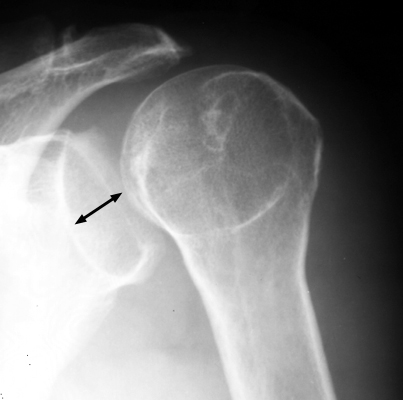

Schulter a.p. (Schultergelenk nach Grashey)

Beurteilungskriterien

- Außenrotation ->Tuberculum majus lateral randbildend, Innenrotation ->Tuberculum minus medial randbildend

- Gelenkspaltweite 4-6 mm

- Weite des subacromialen Raumes exakt nur in der 10 – 15° nach kaudal angulierten Aufnahme bestimmbar ("Morrison, Outlet View")! Normalerweise 1 - 1,5 cm, < 6 mm -> wohl pathologisch, Impingment röntgenlog. wahrscheinlich, Cave. rein klinische Diagnose!

- Normvarianten: Os glenoidale (akzessorischer Ossikel kaudal des Glenoids), persistierende Akromion- oder Korakoidapophyse, entwicklungsbedingte Pfannenranddefekte